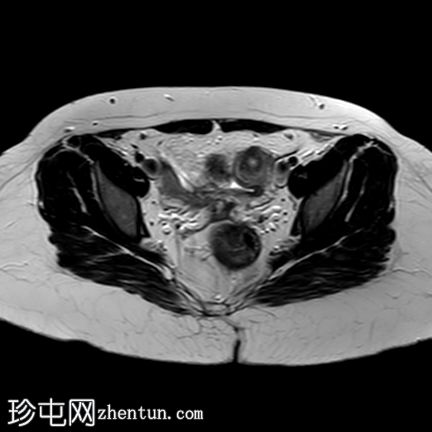

轴位

T1加权像

T2加权像

盆腔两侧可见两个残角,位于双侧卵巢尾侧。可见一条水平带连接两个残角。左侧残角呈腔状,右侧残角呈非腔状。

可见宫颈阴道发育不全,从两个残角延伸出少量发育不良的宫颈组织带。

双侧卵巢功能正常,可见卵泡。

本病例展示了一种 Mayer-Rokitansky-Küster-Hauser 综合征 (MRKH),其特征为子宫缺失和双侧残角;左侧子宫角呈腔状,右侧子宫角呈非腔状。子宫角位于盆腔两侧,双侧卵巢尾侧,并由一条水平带连接。该病伴有宫颈阴道发育不全。